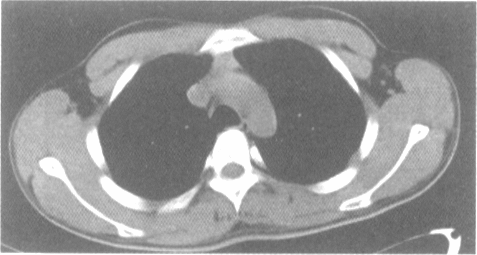

女,43岁,两眼不能完全睁开,全身无力2年余。胸部CT扫描前纵隔内发现肿块,如图,最可能的诊断是

• A.畸胎瘤

• B.心包囊肿

• C.气管囊肿

• D.胸内甲状腺肿

• E.胸腺瘤